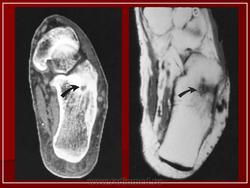

Рентгенологическая картина остеоид-остеомы весьма характерна. Рентгенологические симптомы возникают значительно позже клинических проявлений опухоли, и первым на рентгенограмме обнаруживают склероз кости. На участке поражения формируется одностороннее или муфтообразное утолщение кости в виде гиперостоза. Позднее в толще гиперостоза формируется основной отличительный признак остеоид-остеомы - ее «гнездо» в виде очага разрежения диаметром до 1 см, внутри которого могут отмечаться мелкие костные включения. Сквозь слой склерозированной ткани «гнездо» опухоли на обычных рентгенограммах не всегда дифференцируется и для ее выявления применяют лучи повышенной жесткости и томографию. Обнаружение «гнезда» необходимо для подтверждения диагноза и проведения направленного оперативного вмешательства.